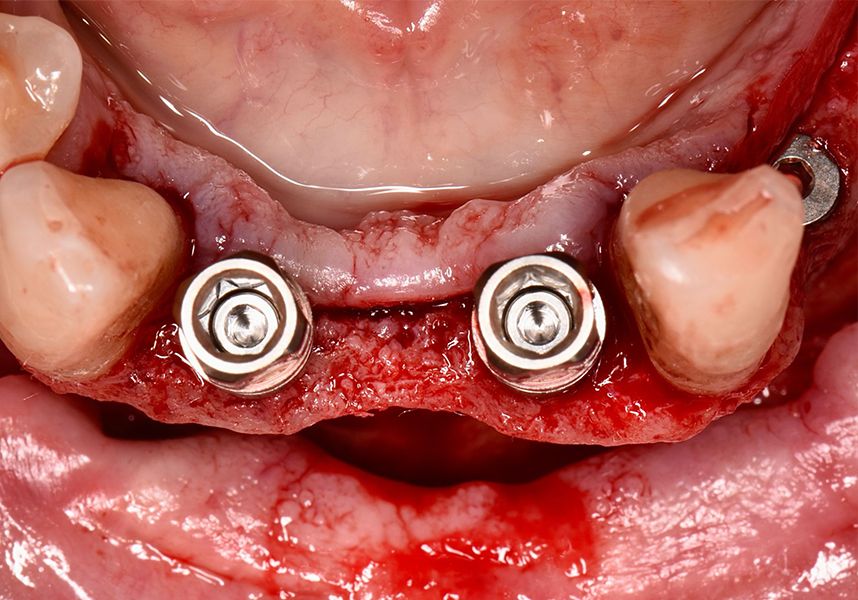

The patient was anesthetized and a flap was made from the distal area of tooth 43 up to 36. Then two Avinent Biomimetic Ocean IC implants of 3.5x10 were inserted in positions 32 and 42.

Respecting the three-dimensionally correct position of the implant led to bone fenestration, leaving the apical part of the apex of the implant exposed almost to the mid-point of its length at 42 and a third in 32.